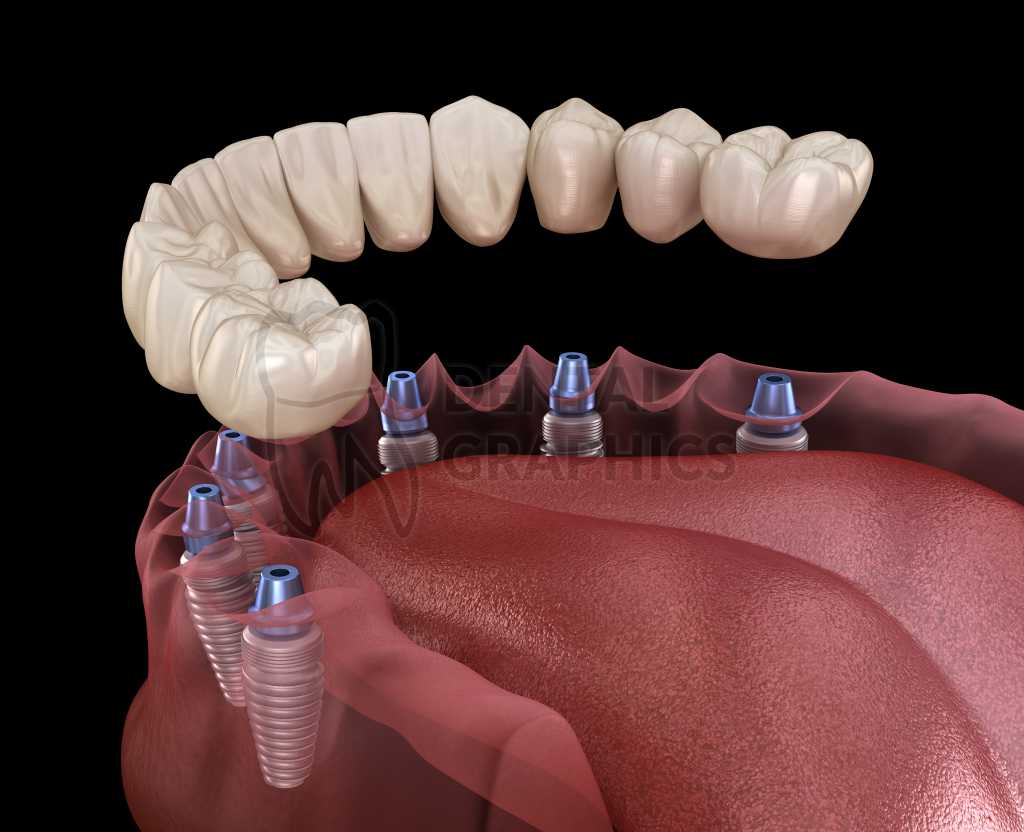

All in six 111 фото